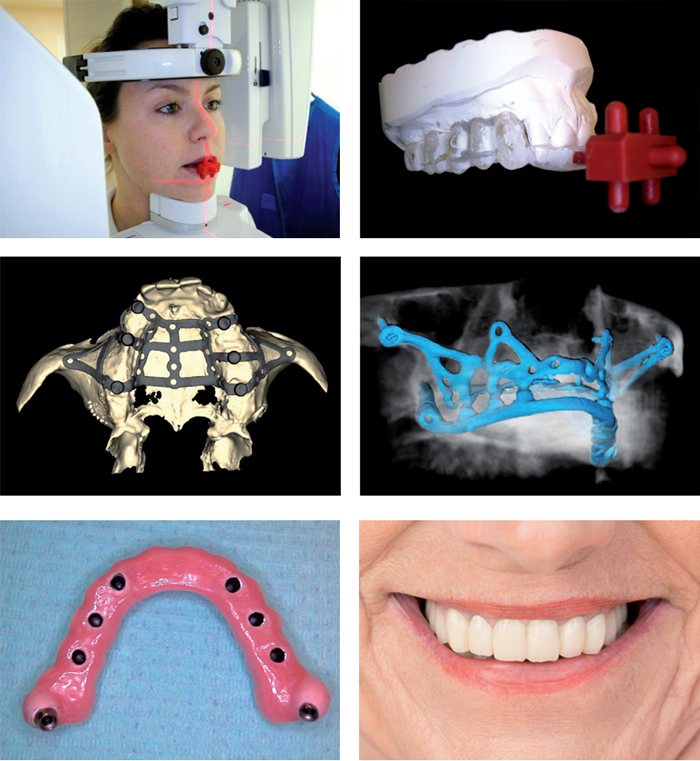

Implantologia Computer Guidata: Riprendi il Controllo del Tuo Sorriso

Se stai cercando una soluzione sicura ed efficace per rimpiazzare i denti mancanti, l'implantologia computer guidata è la scelta ideale. Questa tecnica innovativa combina la precisione della tecnologia computerizzata con l'esperienza clinica dei nostri dentisti, garantendo risultati sorprendenti.

Sempre più spesso si verifica la condizione clinica di persone che, avendo da tempo perso gran parte della dentatura, sono obbligate ad una protesi rimovibile (dentiera o scheletrato) senza possibilità di affrontare un intervento di implantologia per insufficiente percentuale di osso residuo sia in altezza sia in spessore. A questi pazienti venivano prospettati interventi di rigenerazione ossea con innesti, interventi molto invasivi e invalidanti, senza garantire una sicura predizione in termini di successo e tempi di guarigione (in genere nell'ordine dell'anno).

Abbiamo perfezionato il protocollo dell'impianto sottoperiostale (appoggiato sotto la gengiva e non nell'osso), innovandolo ed aggiornandolo con tutte quelle che sono le più recenti tecnologie in nostro possesso, potendo ora garantire un miglior prodotto e un nuovo intervento del tutto differente dal passato.

Un nuovo protocollo impiantare

Eagle Grid è costituito da una struttura metallica (griglia) in titanio, personalizzata per ciascun paziente che si appoggia all'osso mascellare o mandibolare e viene fissata con viti da sintesi.

Il titanio: rappresenta ormai da anni il metallo per eccellenza in implantologia, per le caratteristiche di biocompatibilità con l'osso e per la pressoché assenza di fenomeni di allergia. La griglia è personalizzata: è cioè costruita avendo come stampo l'osso residuo in bocca al paziente. La progettazione e la produzione è gestita da uno staff composto da ingegneri biomedici, medici specialistici, odontotecnici ed esperti informatici, per raggiungere il massimo della precisione con professionalità in ogni fase di lavorazione.

L'Eagle Grid può risolvere casi di totale mancanza dentale mascellare mandibolare o ripristinare i denti in isolati settori della bocca che ne sono privi. Una volta appoggiata intimamente all'osso viene fissata con viti in titanio che nel tempo si osteointegreranno alla stregua di piccoli minimpianti. Eagle Grid non necessita di osteointegrazione in quanto la sua ritenzione è meccanica, consente infatti il carico immediato: cioè la possibilità di utilizzare subito una protesi provvisoria cementata direttamente sui monconi della griglia.